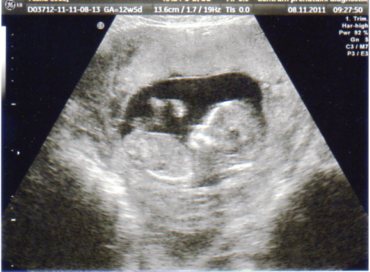

Ahoj holky, tak jsem byla na UZ, mimíska jsem viděla, mával ručičkama a hladil se po hlavičce, bylo krásné vidět ten nový život. nemáte některá fotku z UZ, myslím tak pro srovnání našich mimísků. Ten můj je prý fyziologicky trošku větší, ale je to ještě v normě, tak snad to bude v pořádku. A ještě jsem se chtěla zeptat, vyznáte se některá v těch krevních skupinách? Já mám B neg. a kvůli tomu musel můj přítel na krev, aby zjistili, co má za skupinu, že je to nějaké nebezpečné.